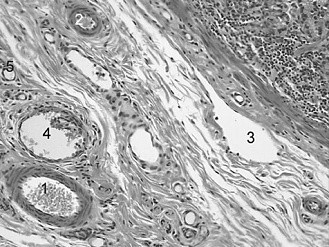

Clinical edema results when lymphatic vessels are blocked or when the volume of extracellular fluid exceeds the drainage capacity of the lymphatic vessels. Which of the following numbered structures in following figure is a lymphatic vessel?

An irregular outline, a thin wall, and the lack of erythrocytes in the lumen characterize lymphatic vessel.

Arterioles (choices A and B) have thicker walls and contain erythrocytes. Venules (choice D) are thin-walled but they contain erythrocytes. Capillaries (choice E) are small in diameter and they contain erythrocytes.